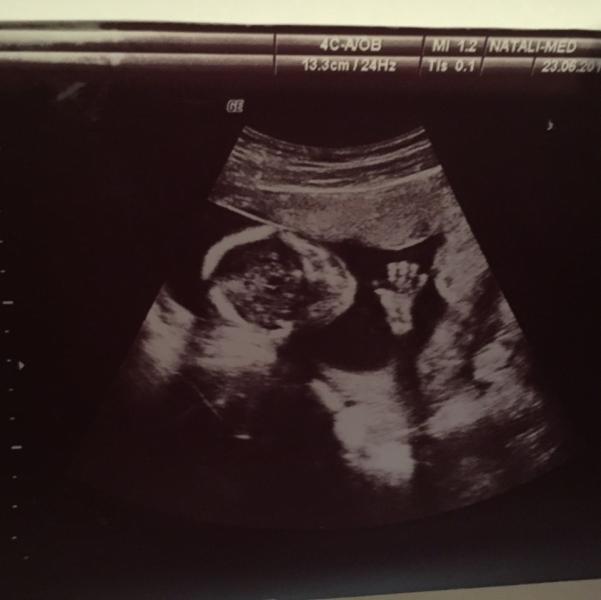

И всем здрасьте!Ну девочки готовьтесь...налейте большую чашку чая и вкусняшки не забудьте,буду сегодня рассказывать про свою первую беременность!итак,историю её начала,а точнее как мы узнали,что нас станет трое вы можете прочитать в моем первом ознакомительно блоке!после первого узи,на котором я увидела во всей красе свою матку и маленькую горошенку(у которой сердцебиение еще не определялось-по сроку ставили 3-4 недели) к врачу мы пошли уже через 2 недели!я еще до беременности начала пить элевит,поэтому витамины пить я так и продолжила,а врач выписала дополнительно только магне в6...я начала сдавать все анализы и проходить всех врачей,для того чтобы можно было заключить контракт на ведение беременности!итак на контрольном узи в 6 недель мы первый раз услышали сердцебиение 146уд/мин...у меня в тот момент наверное сравнялось мое и нашей деточки😄ну и началось...литры венозной крови,мазки из всех возможных мест,обход врачей разных направлений...и когда все анализы и врачи были пройдены,мы заключили контракт с врачем,который нам понравился!само беременность(особенно первые 28 недель)мне дались абсолютно легко и без каких то интересных историй и моментов!я в 12 недель летала отдыхать и чувствовала себя в целом легко и совсем не беременной!токсикоза как такового не было,тошнить меня начало на 12 неделе от элевита!врач посоветовала перейти на фемибион 2,они тогда только появились у нас в аптеках,на них я и сидела всю оставшуюся беременность и лактацию!Несколько раз как-то мне плохо становилось именно до 12 часов!первый скрининг прошел удачно,никаких патологий и отклонений не выявлено!спала кстати оооооочень много!5 января в 19:00 я приехала на плановое узи и на снятие мерок к врачу(нам 28 недель) и что вы думаете?!у меня нарушение маточно-плацентарного кровотока 2 степени и угроза преждевременных,конечно несмотря на то,что сама я вешу 45кг,малышка по животу отставала на 2 недели и под вопросом стояла задержка внутриутробного развития(они не понимали,Либо просто в меня маленькая,либо не хватает ей чего то!хотя ела я постоянно,муж недоедал,а я как с блокадного Ленинграда все в себя😄(ну это и со второй беременностью я пережила😄(при том что чувствую я себя отлично и анализы в норме)!я была просто в диком шоке,когда она сказала,что надо бы лечь на сохранение на капельницы!и не завтра,а прям сейчас!я просто,чуть не упала там!ну значит поехали мы в роддом,конечно заехала за вещами(а их у меня ооооочень много,я брала с собой помойму по максимуму😄даже постельное белье;да я брезгун в этом плане) поехали в 72 при ГКБ,у меня там знакомая работает!она меня в палату двухместную засунула...а я посидев там одна 10 минут,без дополнительных каких то удобств)поняла что мне нужны девочки для общения!тем более разница палат только в количестве человек!перевели меня в палату для 4!в то время там лежало 2 девочки,которые уже со дня на день никак не доедут до родового!ну и я тут такая 28 недель с ними...капали мне актовегин и генипрал....а и веропомил еще!все бы ничего,но капельница с генипралом на 8-10 часов это просто жесть!пролежав 2 недели я засобиралась такая домой ну и меня отправили на узи!и тут бах,а кровотоки то не восстанавливаются!нарушен он и все!ну оставляют меня еще на 10 дней и делают доплер каждые 3 дня!иииииииии....и она как назло меняется каждые 3 дня!то в норме,то опять нарушен!это был ад!короче они на меня наверное весь запас капельниц извели😄28 дней я провела там...с теми кто приезжает и не задерживается больше чем на 7 дней,а если и задерживается,то и те выходили раньше!в общем я там как в армии,такой уже "дед"!!я в какой то из дней отпросилась на несколько часов из роддома к своему врачу!мне необходимо было с ним встретиться и понять,какого хрена меня там держат и решать по поводу продления контракта!приехала я в клинику,сделала узи и мне говорят:-да все нормуль,угрозы нет,а то, что кровотоки скачут(это уже потом все поняла,что скакать просто он так не может,ведь по всем показателям малышка чувствует себя отлично!)это и дома на таблеточках посидишь!и с этим заключением я поехала тыкать в нос зав.паталогией!она меня кое как выписала!а это скажу я вас начало февраля так то!дальше побежали недельки и мы начали готовиться к появлению на свет нашей малышки(до этого времени мы ждали осознания😄)закупали шмотки малышуле(в 12 недель мужа ввели в заблуждение с большей вероятностью сына😄а в 20 недель(на втором скрининге,который также прошел без проблем)знали,что там 100%дочурка,ну точно без яичек),выбирали кроватку,коляску,комод..мелочевку всякую и все что необходимо крошке в первые дни жизни!сделали в 32 недели 3D узи(смотря на монитор чей же там носик и губки)а в 35 недель я поехала разговаривать с главным врачом Одинцовского роддома(ну во-первых сама я заМКАДышь(одинцовская я девчуля),а во-вторых она очень хорошая мамочкина знакомая)и конечно,когда я с ней поговорила,сомнений не было...рожать только у нее!роды с мужем обсуждали,только в случае нахождения меня в Москве(там где я никого не знаю...я больше всего боялась,что нагрублю(а я знаете ли люблю,когда ко мне лицом...)а в момент родов тем более)ну а раз со мной прекрасный специалист,которому я доверилась с пары фраз,мы были спокойны и решили с мужем пожалеть его психику😄она посмотрев все анализы и с чем я находилась в 72 роддоме,сказала,что ждет меня в 36недель,ведь нарушение кровотока могло быть уже хроническим (а как оказалось она просто спала и могла прижать головой пуповину,так кровоток был нарушен;не спит-то доплер в норме)и надо было наблюдать как себя чувствует наша звезда!26 февраля(вск) мы поехали с мужем на фотосессию пуза(ну как же без фотосессии),весь день мы потратили на это!а в пн к 10 моя врач ждала меня с чемоданом в приемном покое!тут я уже не сопротивлялась одноместной палате(во-первых мне хватило месяца наговориться с будущими мамочками,а во-вторых там были все удобства:чайник,стол,стул,шкафчик,телевизор,холодильник,туалет и душевая кабина),прям отдыхай сколько хочешь😀лежала я так 2 недели и что самое интересное,что за все это время ни один допллер не показал никаких нарушений(ну вот как такое мб,а я вам позже расскажу)Ну и как бы 12 марта уже,а я все лежу 38 неделя идет!я врачу то и говорю:-ну если все ок,то может до 40 недель домой меня отпустите?!а она мне:"-ну я так и знала!детка моя,мы тут столько повидали,вот отпущу,а там мало ли что!может рожать?"а я то и не против...с удовольствием!ну и порешали 15 марта идеальный день,чтобы родить принцессу!вечер 14 марта был судорожно-волнительным!я собрала обратно чемодан и передала мужу..как сейчас помню оставила только телефон,зарядку,все для душа и пакетик на роды(детская шапочка,носочки,масло для губ,термальная вода и вода с лимоном во внутрь😄)Утро 15 марта...перенесла я клизму стойко,как то легко даже!потом душ,а там у меня играла welcome to santrope...потанцевали мы в общем с пузяшей!чистые и красивые(а халаты в родильном просто огонь )мы поехали в родовую!прокололи мне пузырь и в ожидании схваток я легла смотреть фильм!с 9-12 мы ждали начала схваток,но честно,подтягивало там чего то непонятно ..."-раскрытие пол мышиного глазика" сказала моя врач!говорит если так и пойдет поедем на кс!а я ей:"-так может сразу и поедем?!"ну я так подумала,раньше поеду,раньше в реанимацию переведут,а там и до палаты недалеко!она на меня посмотрела и говорит:"сейчас к тебе чудо анастезиолог придет,а там посмотрим..."ну и тут входит он!тот без которого моя шейка никак не хотела раскрываться!"-сейчас будем тебя раскрывать!"-говорит!ну провел опрос и ввел мне эпидуралку,да в тех количествах,что я вообще ничего не чувствовала,тем более тех схваток,я ногами то передвигать не могла😄и я легла поспать!через 1,5 часа я проснулась от того,что меня подташнивает...ужс!а еще я такааааая голодная была!и тут входит моя врач и говорит:-детка моя,ну давай посмотрим!"смотрит, а там открытие уже 9!через пол часа я почувствовала их...нееее,не схватки!это были потуги!меня посмотрели,сказали продыши 20 потуг и поедем!ну в общем-то продышала я их нормуль,привезли в родблок!ну врач сразу сказала,что надо делать эпизио,иначе просто порвусь вся(при том,что родила я 2530😄как она сказала,что 2700 уже не прошла бы)быстренько на потуге меня чикнули(совсем не больно) и вы думаете все?!нееет!пару раз она завалилась мне на живот,ведь потуги мне не хватало!и когда зашел её зам(Алексей Владиморович-он принимал у меня уже вторую дочку,но об этом в следующем рассказе)он решил,что возьмет давку на живот на себя!а моя врач ему и говорит:"давай,только не сильно)и вот потуга,он как надаааавит,она и вылезла!а врач ему:"ну Лёша,ну я же просила не сильно!"😄 и тут первый крик(17:40),наше чудо у меня на пузе(я кстати не рыдаю,а странно ведь я представляла себе первую встречу как в фильмах😀 )малышку унесли взвешивать(2530 и 49) и делать все необходимые процедуры!меня зашила(было не то,чтобы прям адски больно,но диииико не приятно!шов у меня кстати один и внешний)после,два часа отхождения с льдом на животе,телефон разрывался от поздравлений и возгласов какая я молодец!(ну я на самом деле такая😄)и вот наконец-то палата!мы с малышкой лежали вдвоем в одноместной палате со всеми удобствами:телевизор,холодильник,чайник,СВЧ,душ,туалет(как в патологии)все для нашего с пупсиком удобства!в палате мы были около 8 часов вечера,а в 22:00 малышуле поехала в детское отделение,оставив меня на ночь отдыхать!и тогда был полный кайф,ведь я смогла за 9 месяцев лечь на живот,а засыпаю я только на нем!во время беременности меня спасла подушка для беременных,а потом до новой беременности с ней спала наша дочка!на следующий день поздравлять приехал новоиспеченный папа!он не мог на нее насмотреться,все 3 часа держал её на руках и не мог поверить,что вот она,та ради которой наша жизнь теперь измениться,ведь мы стали-родителями!